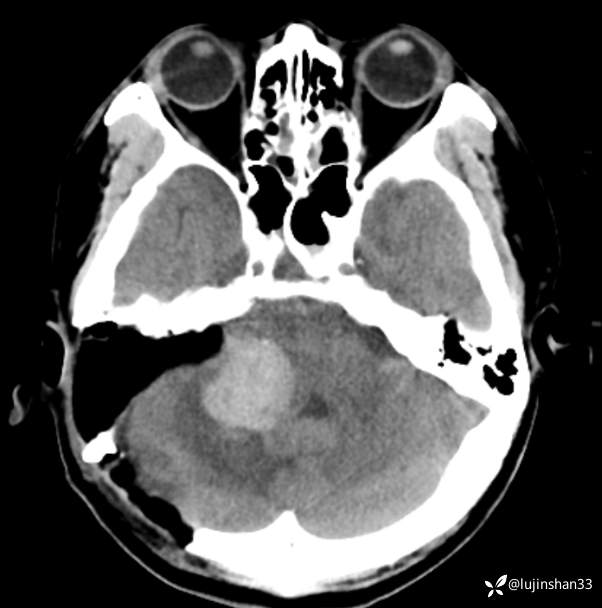

术前CT及MRI

临床诊断:右侧桥小脑角血管母细胞瘤

讨论:桥小脑角区占位,血供情况如何判定?良恶性如何从影像学判定?